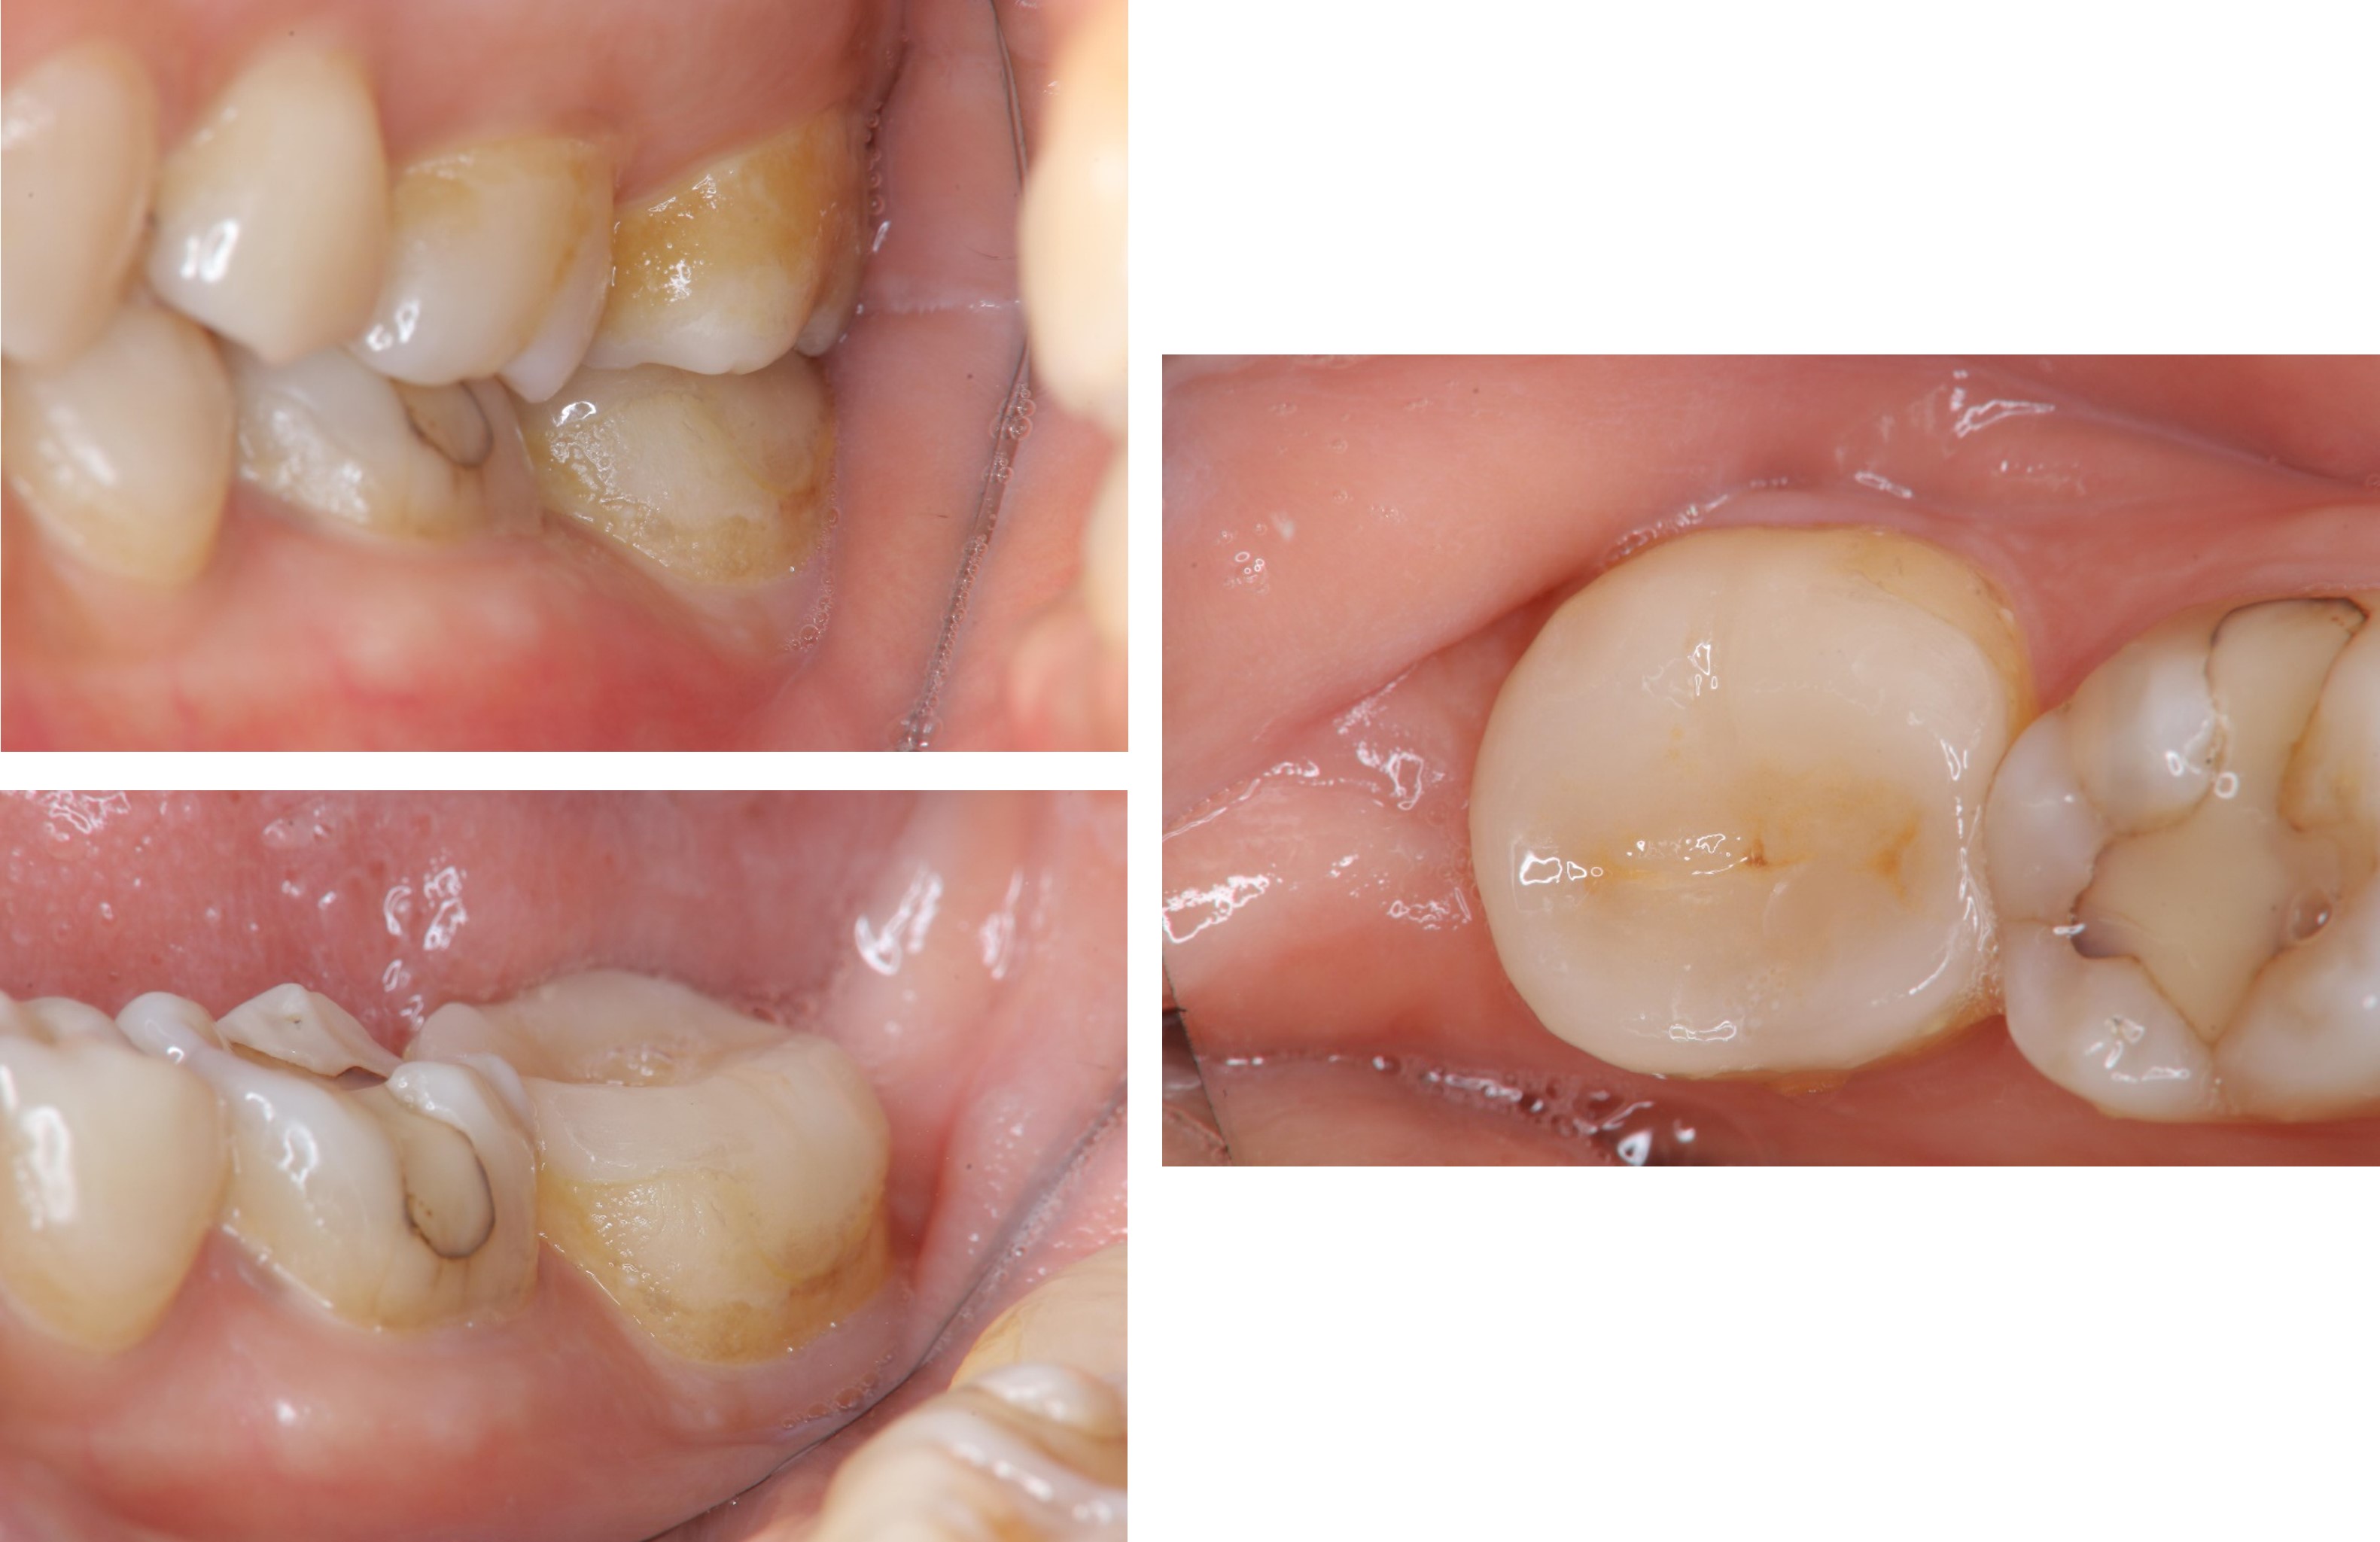

治療後口內照

邊緣完整

術前、術後比較